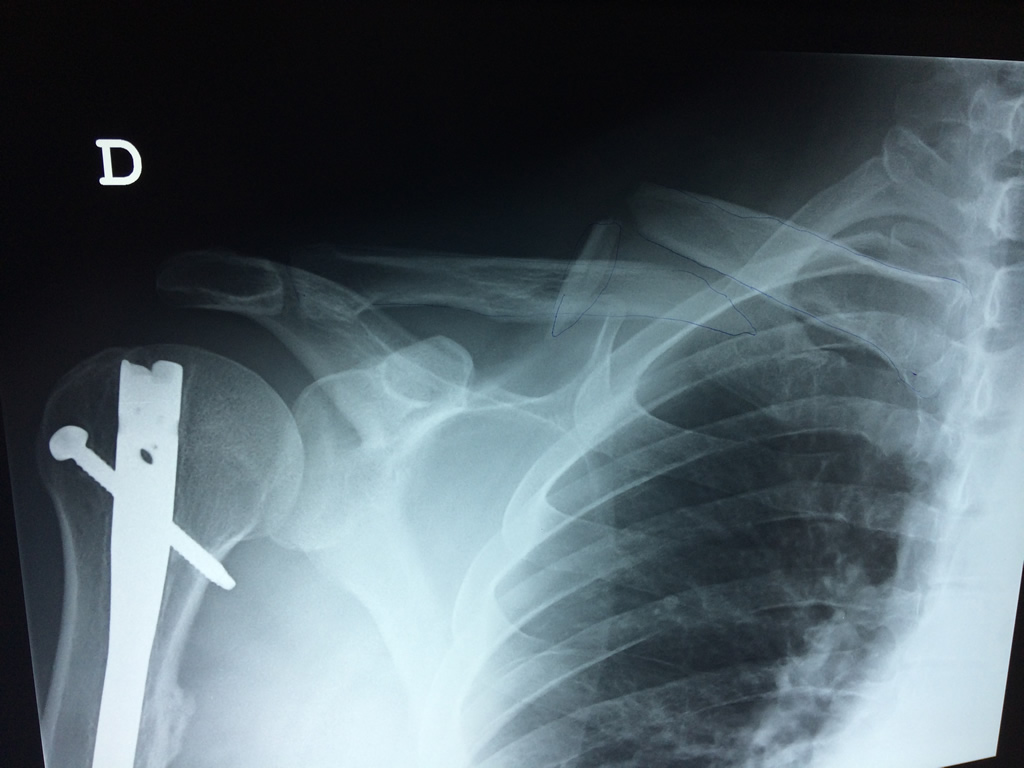

La clavícula es un hueso largo, con forma de "S" itálica, situado en la parte anterosuperior del tórax. Junto con la escápula forman la cintura escapular. Se puede palpar por toda su longitud y se extiende del esternón al acromion de la escápula, siguiendo una dirección oblicua lateral y posterior.

Se considera el único medio de unión entre el miembro superior y el tórax. A pesar de su aspecto, similar al de un hueso largo, posee una estructura semejante a la de un hueso plano, ya que carece de epífisis y de diáfisis, lo que la harían entrar dentro de la clasificación de hueso largo. Carece de un canal medular propiamente dicho.